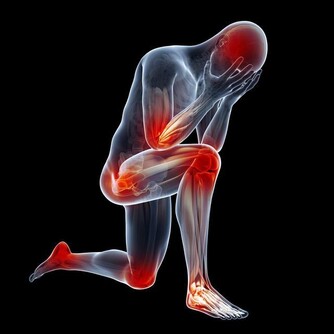

這六種走路姿勢,正在悄悄損傷肌肉和關節!

是的,走路人人都會,但不一定都對,你以為沒問題的走姿,可能正是你腰酸背痛的“罪魁禍首”。

那麼,日常生活中,哪些常見走姿其實是又“難看”又損傷健康的突出錯誤呢?下面就跟著養生君一起來看看吧。